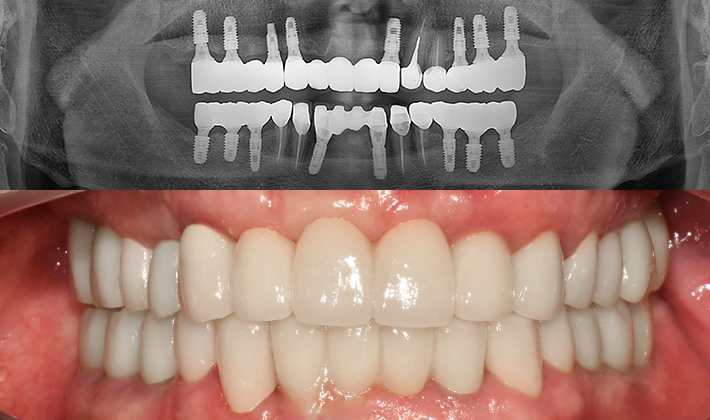

실제 치료 사례

수많은 환자들이 고민 끝에 선택한 치료,

그리고 그 후의 놀라운 변화

- ※ 위 임상사진은 365서울원탑치과에서 진료를 시작하고 마친 동일한 환자의 사진입니다.

- ※ 위 임상사진은 동일한 장소에서 동일한 조건으로 촬영되었으며, 사진에 대한 별도의 조작이 처리되지 않았습니다.

- ※ 수술 및 치료 과정에서 부작용이 발생할 수 있으므로 의료진과의 충분한 상담과 신중한 판단이 요구됩니다.

환자를 향한 진심,

완성도 높은 결과

환자의 상태를 세심하게 살피고,

글로벌 스탠다드에

맞춘

진단과

치료 과정을 통해 보다 안전하고

완성도

높은 결과를 만듭니다.